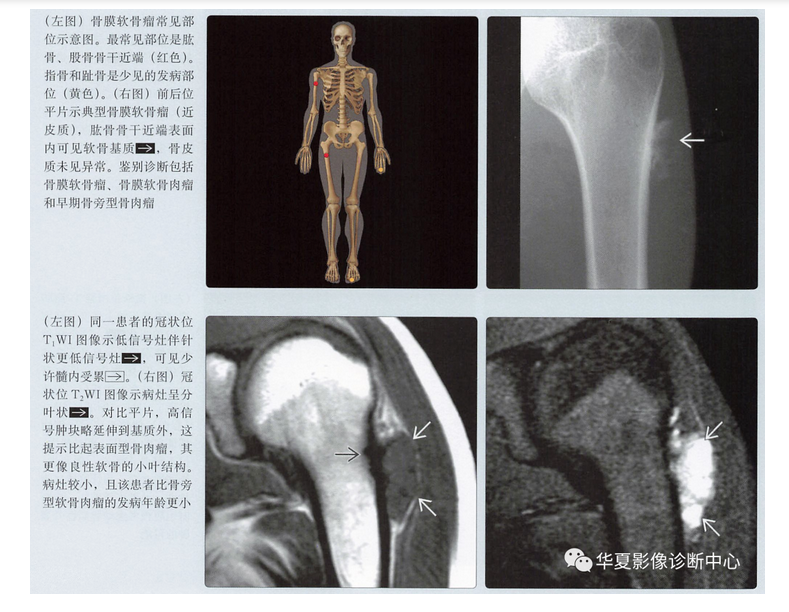

MR表现

- 病灶的结节状形态

- T1上等或低信号

- T2上高信号

- 不均匀强化,通常呈边缘强化

- 髓内累及(20%)

- 髓内水肿(20%)

- 不规则软组织肿块(30%)

骨膜软骨肉瘤

- 很少见的表面型软骨肉瘤

- 与骨膜软骨瘤发病部位相同

- 通常为低度恶性,因此可能不会出现明显侵袭性

- 几乎与骨膜软骨瘤影像表现相同

- 骨表面病灶

- 骨皮质呈扇形塌陷改变

- 基质钙化

- 类似的MR特征

- 低级别软骨形成小叶结构,液体敏感序列上呈高信号

- 边缘强化,伴比较小的软组织肿块

- 与骨膜软骨瘤没有可靠的鉴别点,但是

- 病灶可能比大多数骨膜软骨瘤大

- 比骨膜软骨瘤发病年龄略大